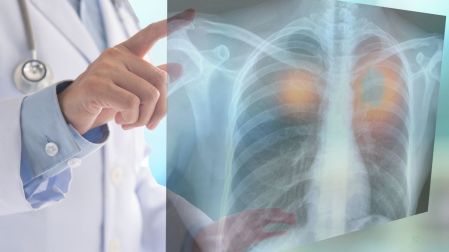

¿Qué hizo posible este cambio? Los médicos han dejado de ver al cáncer de pulmón como una sola enfermedad. Ahora, la clave es encontrar su "apellido molecular".

El doctor Jorge Alatorre, oncólogo especializado en cáncer de pulmón, explica que identificar las alteraciones genéticas específicas de cada tumor permite ofrecer un tratamiento mucho más certero y eficaz.

Ya no hablamos de una sola enfermedad, sino de múltiples subtipos de cáncer de pulmón que se tratan de manera distinta,” señala.

En el subtipo más común, el adenocarcinoma (que afecta al 85% de los casos), los oncólogos buscan una alteración crítica: la mutación del receptor de factor de crecimiento epidérmico (EGFR).

En México, se estima que esta mutación está presente en casi la mitad de los pacientes con adenocarcinoma, lo que los convierte en candidatos ideales para las nuevas terapias.